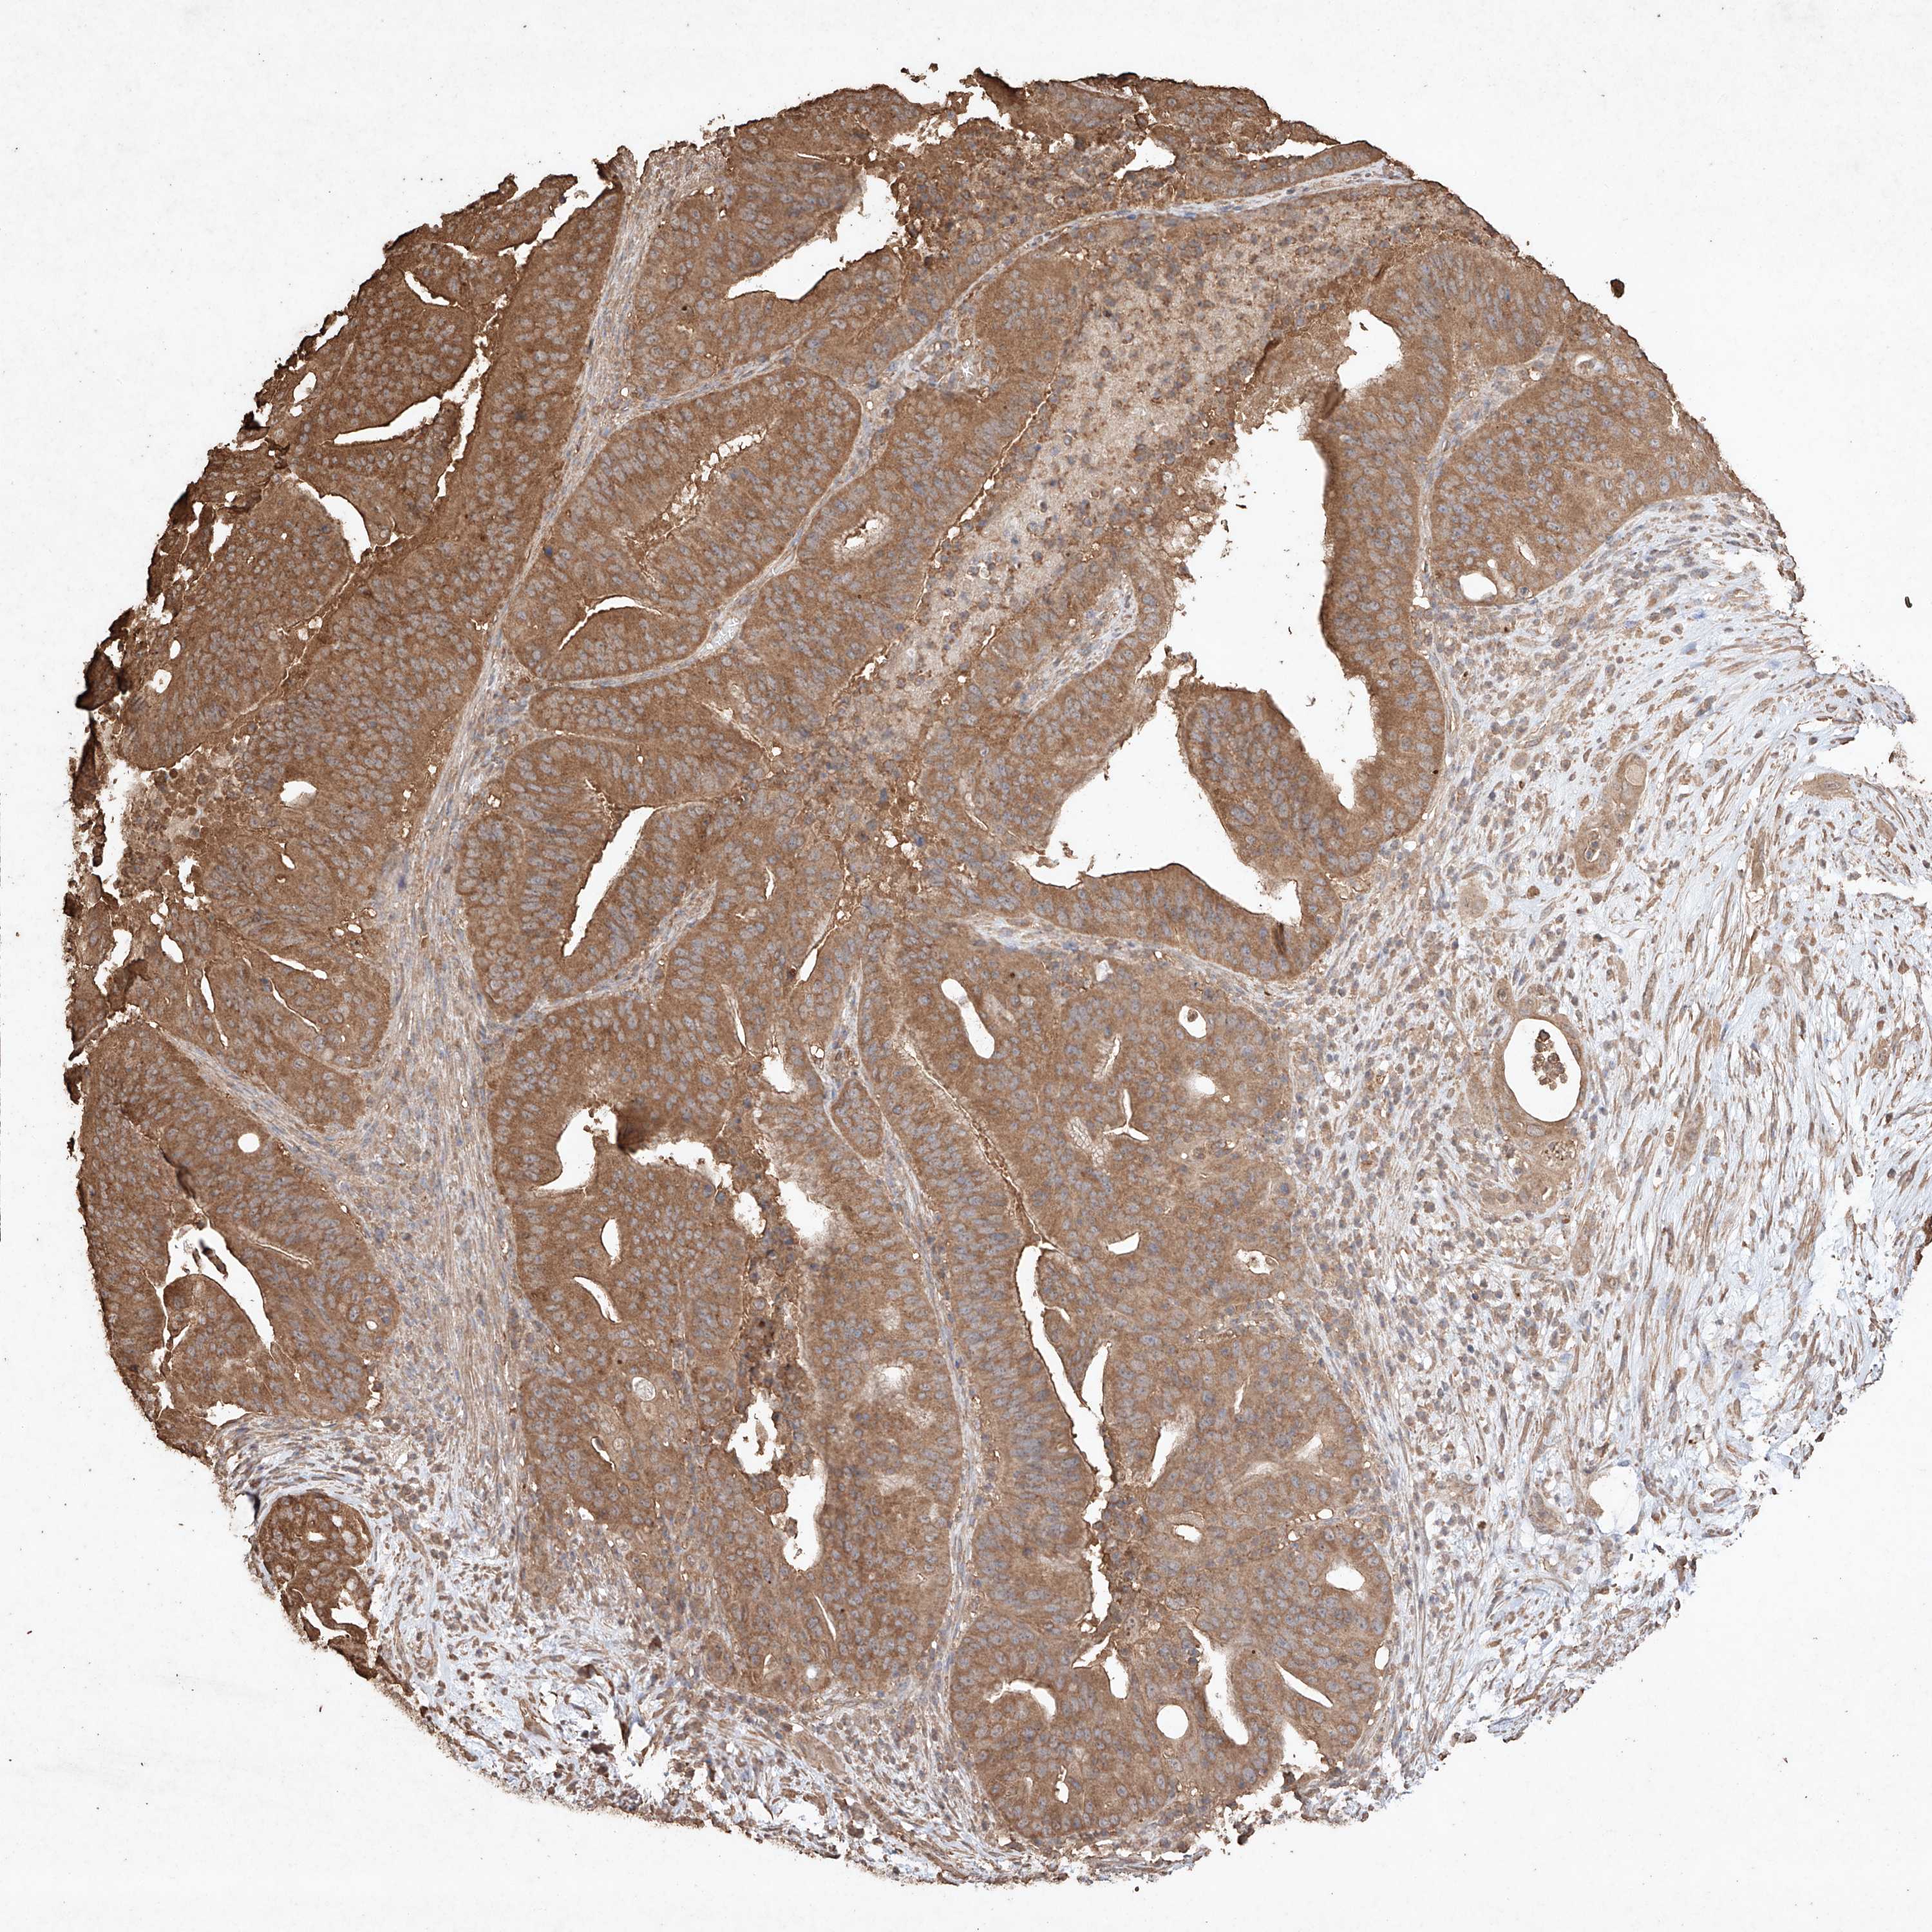

PANCREATIC CANCER - Protein expressioni

A mouse-over function shows sample information and annotation data. Click on an image to view it in a full screen mode. Samples can be filtered based on level of antibody staining by selecting one or several of the following categories: high, medium, low and not detected. The assay and annotation is described here.

Note that samples used for immunohistochemistry by the Human Protein Atlas do not correspond to samples in the TCGA dataset.

Antibody stainingi

Antibody staining in the annotated cell types in the current human tissue is reported as not detected, low, medium, or high, based on conventional immunohistochemistry profiling in selected tissues. This score is based on the combination of the staining intensity and fraction of stained cells.

Each image is clickable and will lead to virtual microscopy that enables deeper exploration of all samples and also displays staining intensity scores, fraction scores and subcellular localization as well as patient and tissue information for each sample.

Antibody HPA040445

Antibody CAB034464

Staining

High

Medium

Low

Not detected

Intensity

Strong

Moderate

Weak

Negative

Quantity

>75%

75%-25%

<25%

None

Location

Nuclear

Cytoplasmic/membranous

Cytoplasmic/membranous,nuclear

Adenocarcinoma, NOS